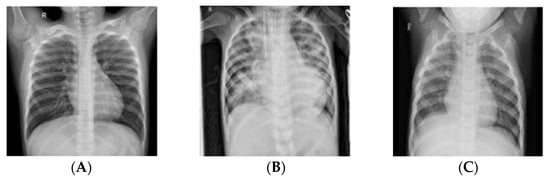

Even though Chest X-rays (CXRs) have a weaker resolution as compared to Magnetic Resonance Imaging (MRI) or Computerized Tomography (CT) scans, they can be used to perform multiple assessments such as cardiomegaly, pneumonia, pneumothorax, and atelectasis. Diagnosing pneumonia using radiographs is highly subjective and depends on the knowledge and expertise of the radiologist. It is easier to diagnose pneumonia using high resolution MRI and CT scans; however, most radiologists use CXRs to perform assessments owing to quicker turn-over and cost effectiveness of the modality. On a typical radiograph, pneumonia is marked by radio-opacities or white spots in the airways, particularly in the alveoli, which indicates the presence of inflammatory exudate. These radiological findings may present a challenge to a novice radiologist, leading to false positives and false negatives owing to the fact that other diseases mimic these signs. Figure 1 shows samples of CXR images that were utilized in this study and classified as normal, bacterial pneumonia, and viral pneumonia from the pediatric group.

Figure 1. Pediatric Chest X-ray images; normal (A), bacterial pneumonia (B), and viral pneumonia (C).